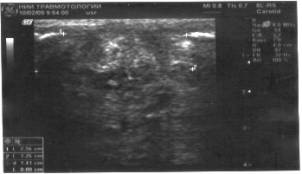

Рис.1 Эхограмма регенерата большеберцовой

кости, у пациента с хроническим остеомиелитом,4 мес. после операции, активность

остеогенеза снижена (А). Допплерогамма сосуда в регенерате, отмечается

сниженный кровоток.(Б)